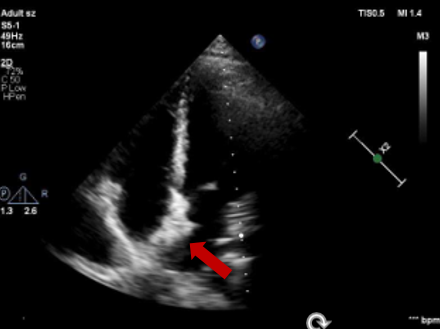

封堵器释放

封堵器释放后形态良好

未见残余分流,封堵成功